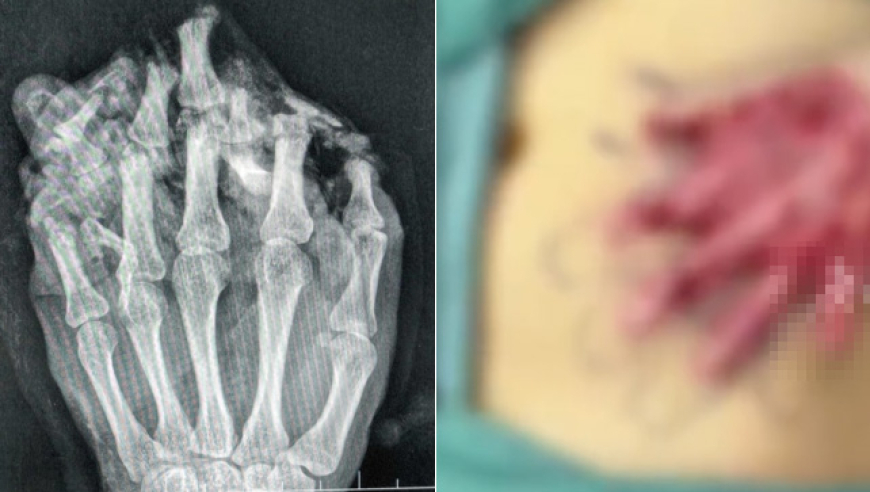

近日,广东东莞4岁的工人小王工作时,左手不慎被机器碾压,导致左手严重受伤,导致左手严重受伤,手掌、手背、各指掌侧及背侧皮肤脱套流血、疼痛,被紧急送到医院。(拍片显示左手伤情严重)医生诊断他为:1.左手掌、手背,示指中指环指小指掌侧及背侧皮肤毁损脱套伤;2.左手掌、手背及各指肌腱神经血管损伤;3.左手多发性...

24岁男子手指不慎被机器碾压,医生将“伤手”寄养在其肚子1个月,成功把粘连手指分开后再进行手术